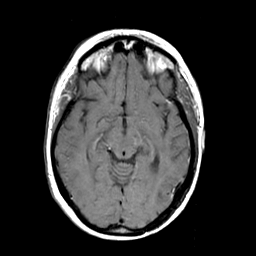

MR Study #3 -- Slice #24

[Home][Help][Clinical][Tour 1][Tour 2][Tour 3] Slice 24